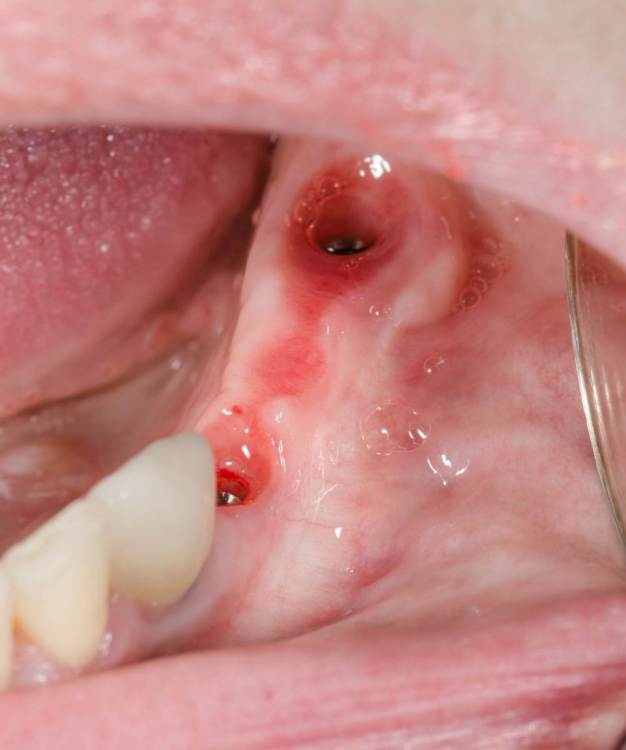

примерно через 6 дней

1988054488_3.thumb.jpg.2e3ab7dfd32d9339c7f10a00fb3fe313.jpg

через 2 недели

1271770516_4.thumb.jpg.a6b168771ab3f235fb82cabde8e48291.jpg